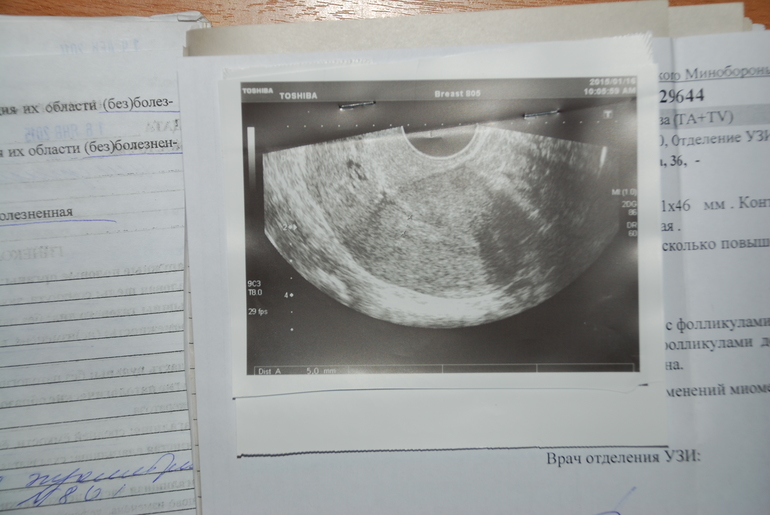

вот это второе, январь 2015г., после 2-х месяцев дюфастона: